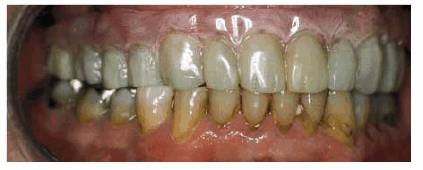

patient (Figures 17-1A to

C

Figure 17-1A to C: These photographs illustrate the complex dental condition of a 71-year-old male: (A) The palatal cervical regions of the maxillary anterior teeth exhibit sharp, wedge-like lesions that are characteristic of abfraction. These areas would be difficult, if not impossible, to have resulted from toothbrush abrasion. (B) The buccal aspects of the maxillary posterior teeth show smooth, concave configurations that are consistent with toothbrush abrasion and/or erosion. (C) The buccal surfaces of the mandibular teeth have lesions that possess components of both abfraction (sharp margins in the occlusal regions) and abrasion (concave geometry and gingival recession in the cervical regions).